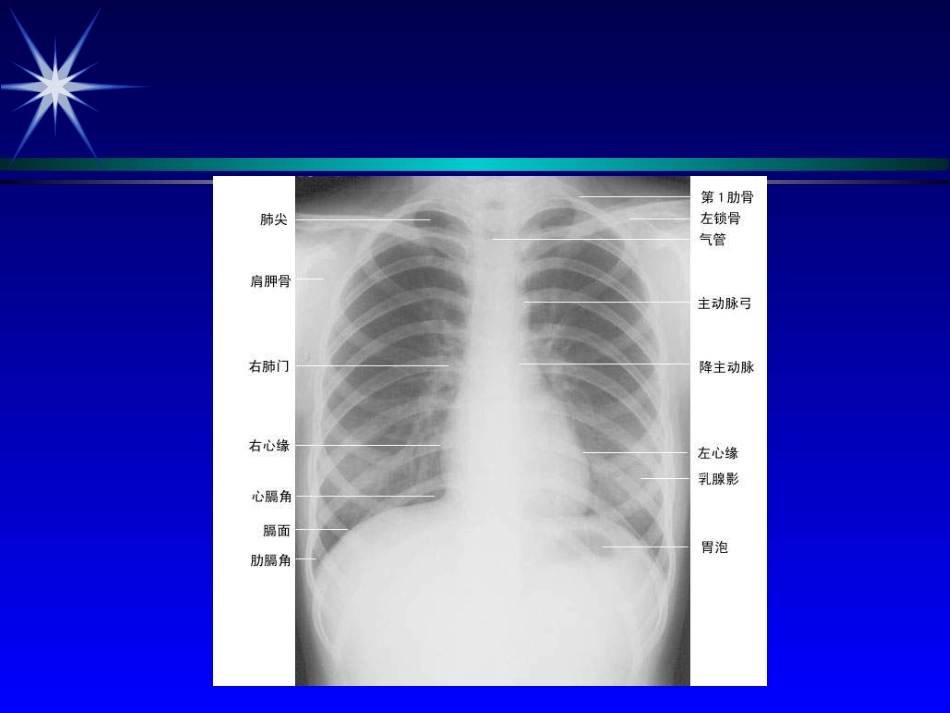

ExaminationExaminationoftheHeartoftheHeartJinYu-huaJinYu-huaDept.ofGeriatricsDept.ofGeriatricsExaminationoftheHeartExaminationoftheHeartExaminationoftheHeartExaminationoftheHeartLandmarksandtopographicanatomyLandmarksandtopographicanatomyCertainbasiclandmarksCertainbasiclandmarksmidsternalline(midsternalline(前正中线前正中线))midclavicularlines(midclavicularlines(锁骨中线锁骨中线))anterior,middle,andposterioranterior,middle,andposterioraxillarylines(axillarylines(腋前、中、后线腋前、中、后线))suprasternalnotchsuprasternalnotch(胸骨上窝)(胸骨上窝)identificationofvariousribsandidentificationofvariousribsandintercostalspaceintercostalspaceprecordiumpreco...